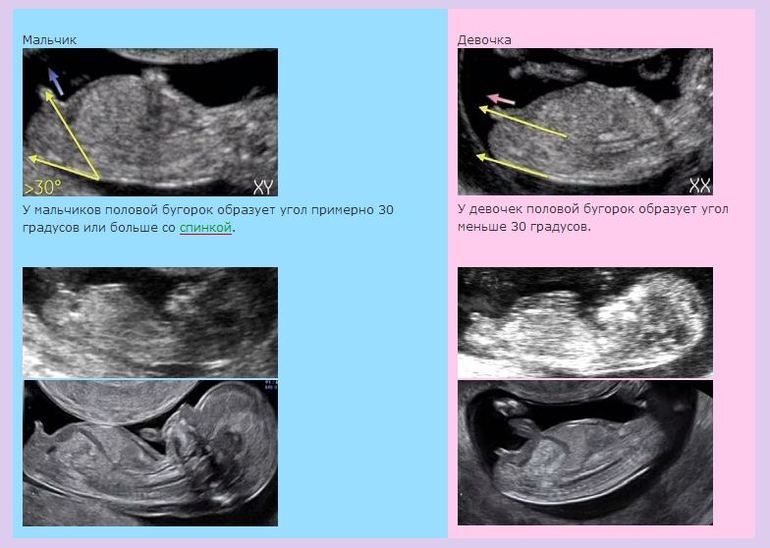

Мне видится, что половой бугорок девчачий всё же.

Вот гляньте, как различить.